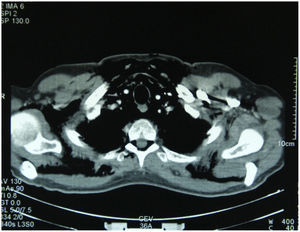

Seis meses después acude a urgencias por presentar disfonía, aumento del perímetro del cuello y sensación de crepitación. No refería antecedente traumático, ni otros síntomas respiratorios o digestivos. A la exploración física presentaba: febrícula (37,5°C); frecuencia cardíaca, 105lat/min; frecuencia respiratoria y presión arterial (PA) normales. La pulsioximetría mostró una saturación de oxígeno normal. No se evidenció acropaquias ni signos de vasculopatía cutánea. Se objetivaron lesiones cutáneas compatibles con pápulas de Gottron en manos y codos y enfisema subcutáneo en cara, cuello, tronco y extremidades superiores. El resto de la exploración física por aparatos no mostró alteraciones. Se le realizó radiografía de tórax y tomografía computarizada (TC) toraco-abdominal, que evidenciaron neumomediastino, neumorraquis, extenso enfisema subcutáneo, pequeño neumotórax bilateral apical y afección parenquimatosa pulmonar bilateral tenue de distribución periférica (fig. 1). Se realizaron, además, esofagograma, broncoscopia, electrocardiograma y ecocardiograma que no mostraron alteraciones. No se realizó estudio funcional respiratorio por el riesgo que suponían las maniobras de hiperpresión torácica. Una resonancia magnética (RM) de pelvis y muslos mostró líquido perifascial bilateral, simétrico, que afectaba a los semimembranosos, vastos laterales y rectos anteriores sin evidenciarse edema muscular. El electromiograma (EMG) constató actividad espontánea esporádica y potenciales de unidad motora de aspecto miopático en la musculatura proximal de las extremidades superiores e inferiores.

Tras 9 meses de tratamiento inmunosupresor (CFM en pulsos trimestrales, CyA a dosis de 5mg/kg/día y corticoides en pauta descendente), no recidivó el neumomediastino, el paciente permaneció estable y recuperó su capacidad para deambular. La gasometría arterial basal mostró PO2 de 60mmHg y PCO2 de 37mmHg, con saturación de oxígeno del 91%. Las pruebas de función respiratoria mostraron un patrón restrictivo con disminución de la difusión pulmonar de oxígeno. En la TC persistió una amplia panalización bilateral (fig. 2), con la desaparición de las lesiones en vidrio deslustrado. Dadas la gravedad de la alteración funcional respiratoria residual y la estabilidad de las imágenes radiológicas, se remitió al paciente a su hospital de referencia para valorar trasplante pulmonar.